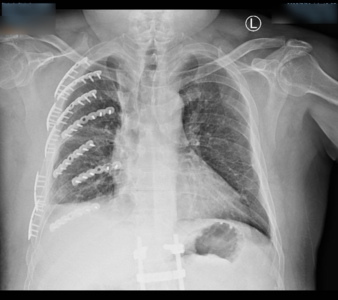

國道1號日前發生驚險工安意外!一名51歲陳姓國道工作人員在處理掉落的高危險布鉤繩時,竟遭疾駛而來的遊覽車猛烈撞擊,造成全身多處粉碎性骨折,光是肋骨就斷了14處。經過衛福部彰化醫院緊急進行3D微創胸腔重建手術後,原本連呼吸都痛到必須「憋氣」的陳男,重展笑顏「終於可以自由呼吸了」! 《詳全文...》